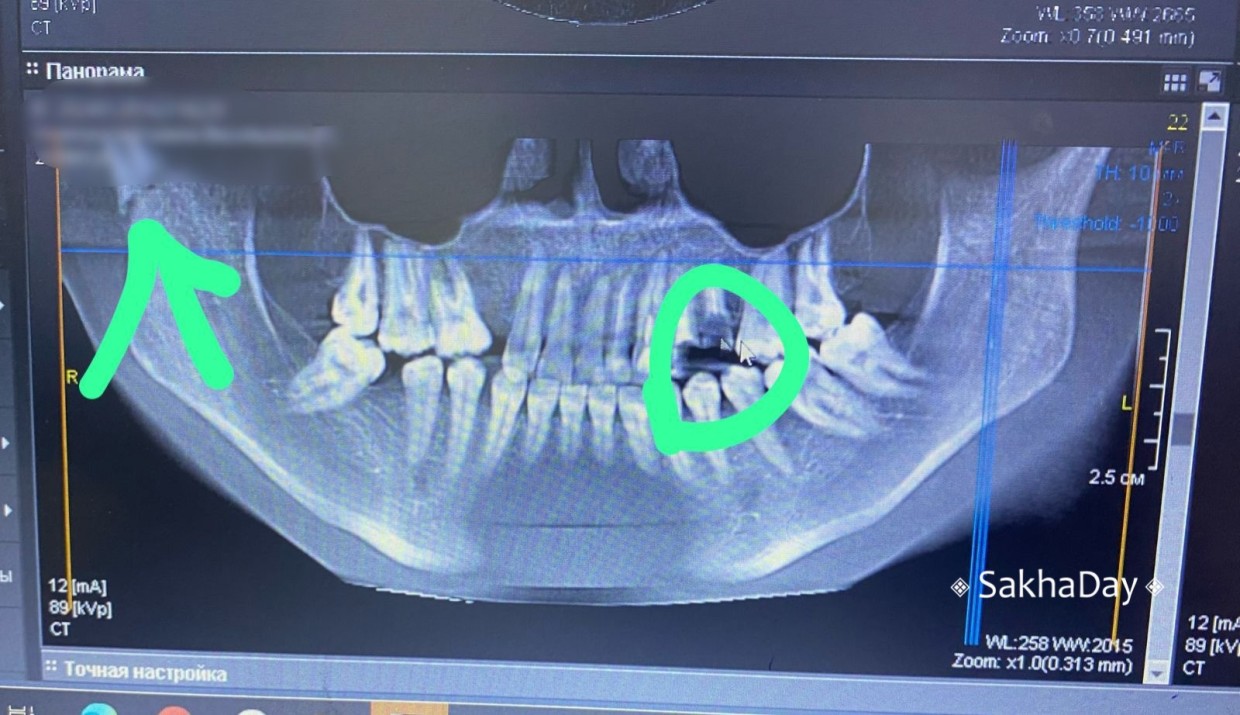

24 марта стало известно, что приняты меры в отношении сотрудников Республиканской больницы №2 за неоказание медпомощи. Напомним, что 5 января 2024 года в приемный покой обращалась жительница Якутска, которую избил бывший молодой человек, держа на руках годовалую дочь. Так, челюстно-лицевой хирург отказал пациентке в рентгене из-за чего не был диагностирован перелом челюсти, передает SakhaDay.

Затем в другой день пострадавшая Айталина вновь обращалась в Республиканскую больницу №2, но ей снова отказали в рентгене из-за поломки компьютера. В конце концов, двухсторонний перелом челюсти диагностировали в частой клинике.

Из текста документа следует, что на основании публикации в «SakhaDay» о не установлении диагноза двустороннего перелома нижней челюсти при обращении 5 января 2024 года в приемное отделение ГБУ РС (Я) «РБ №2-ЦЭМП» в рамках своих полномочий территориальным органом была инициирована и проведена внеплановая документарная проверка в отношении больницы.